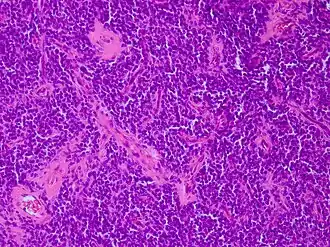

Aspect microscopique

Les sarcomes d'Ewing, et plus généralement les tumeurs neuroectodermiques primitives (PNET), montrent une prolifération d'architecture diffuse, composée de petites cellules rondes au rapport nucléocytoplasmique élevé[5].